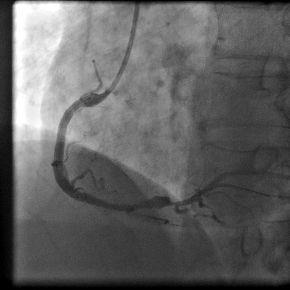

病例介绍:陈姓35岁青年男性,因“突发胸痛2小时”与凌晨1:00入我院急诊科,入院后即刻心电图提示急性下壁、后壁心肌梗死,认为应立即行急诊PCI术。立即给予足量阿斯匹林和波立维,启动急性心肌梗死救治绿色通道。导管室护士、技师、心内科医生在导管室等待,并且做好术前准备。在得到患者家属同意后,我们迅速带患者入导管室。急诊冠脉造影示:右冠状动脉近段完全闭塞,通过血栓抽吸,球囊扩张,开通闭塞血管,右冠近段成功植入药物涂层支架一枚,患者转危为安,整个过程用时28分钟。